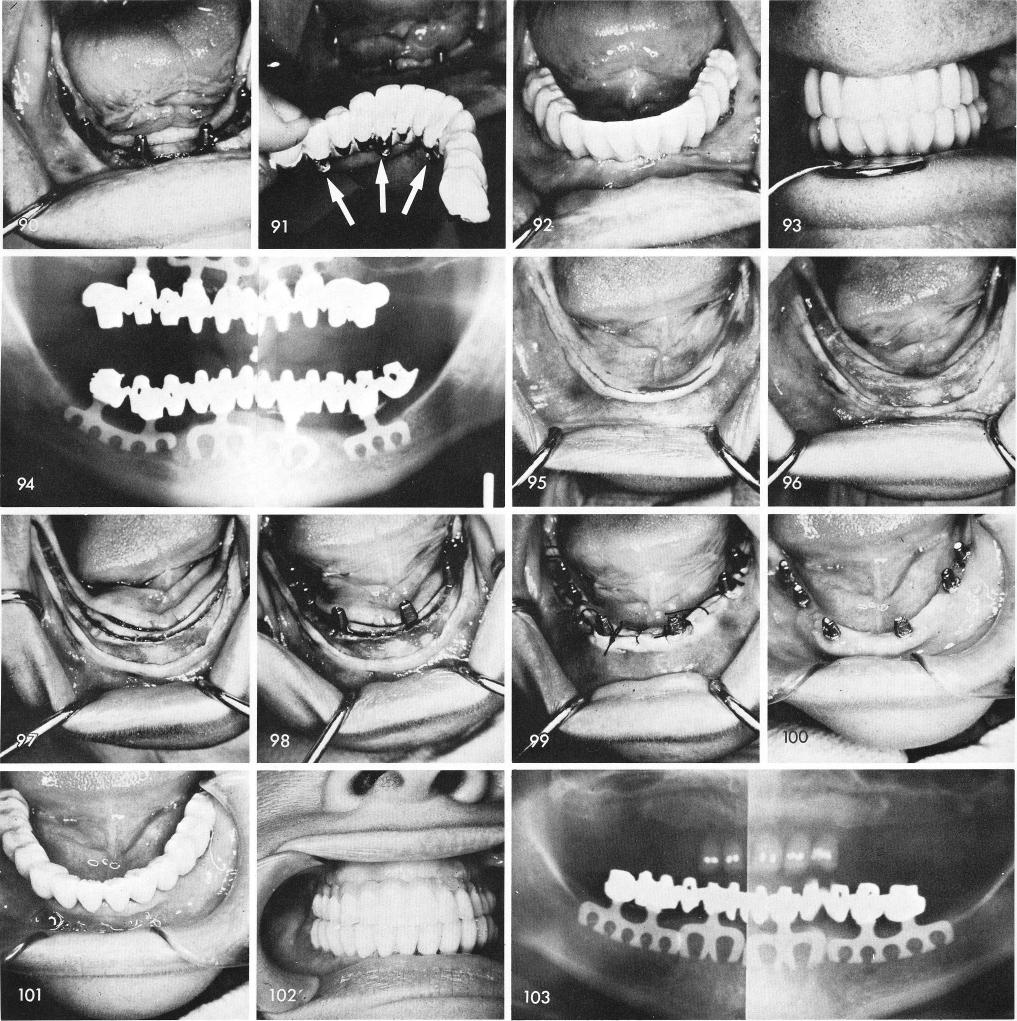

Some of my earlier designed blades had horizontal threading through the posts, fig. 90, to allow for "screwing in" of the prosthesis without the use of cement, figs. 91, 92, 93. However discoloration of the underlying metal developed as well as cases of halatosis occurred causing me to drop this system. Final x-ray, fig. 94.

Sometimes in totally edentulous cases, figs. 95, 96, a continuous groove rather than interrupted grooves are created, fig. 97, making it a bit easier to line up the blade posts with the opposing teeth, fig. 98. After suturing, fig. 99, and healing, fig. 100, the restoration is cemented, figs. 101, 102. The post-operative x-ray, fig. 103.

1 Mandibular blade implants with horizontal threading through the posts